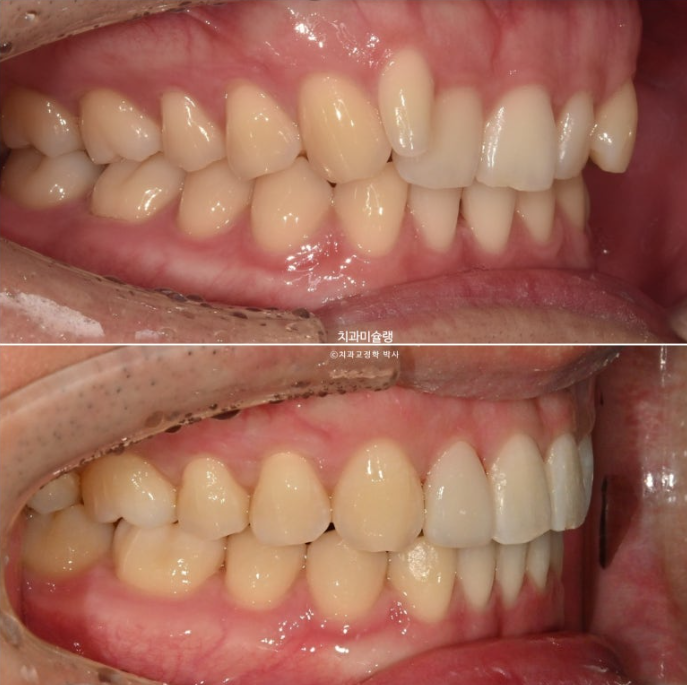

24.03~25.11

아래 앞니 블랙트라이앵글은 치축의 개선과 소량의 치간삭제로 사이즈를 줄였습니다.